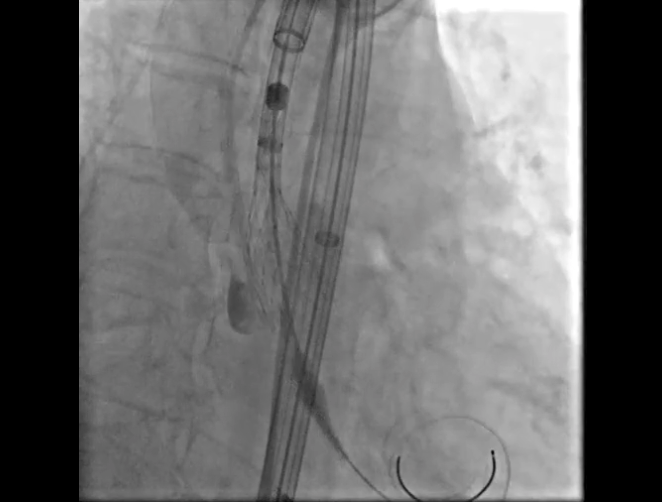

Step 2.建立大鞘通路:大鞘通过升主、边进入边加弯,避免剐蹭弓部斑块

14.gif

15.gif